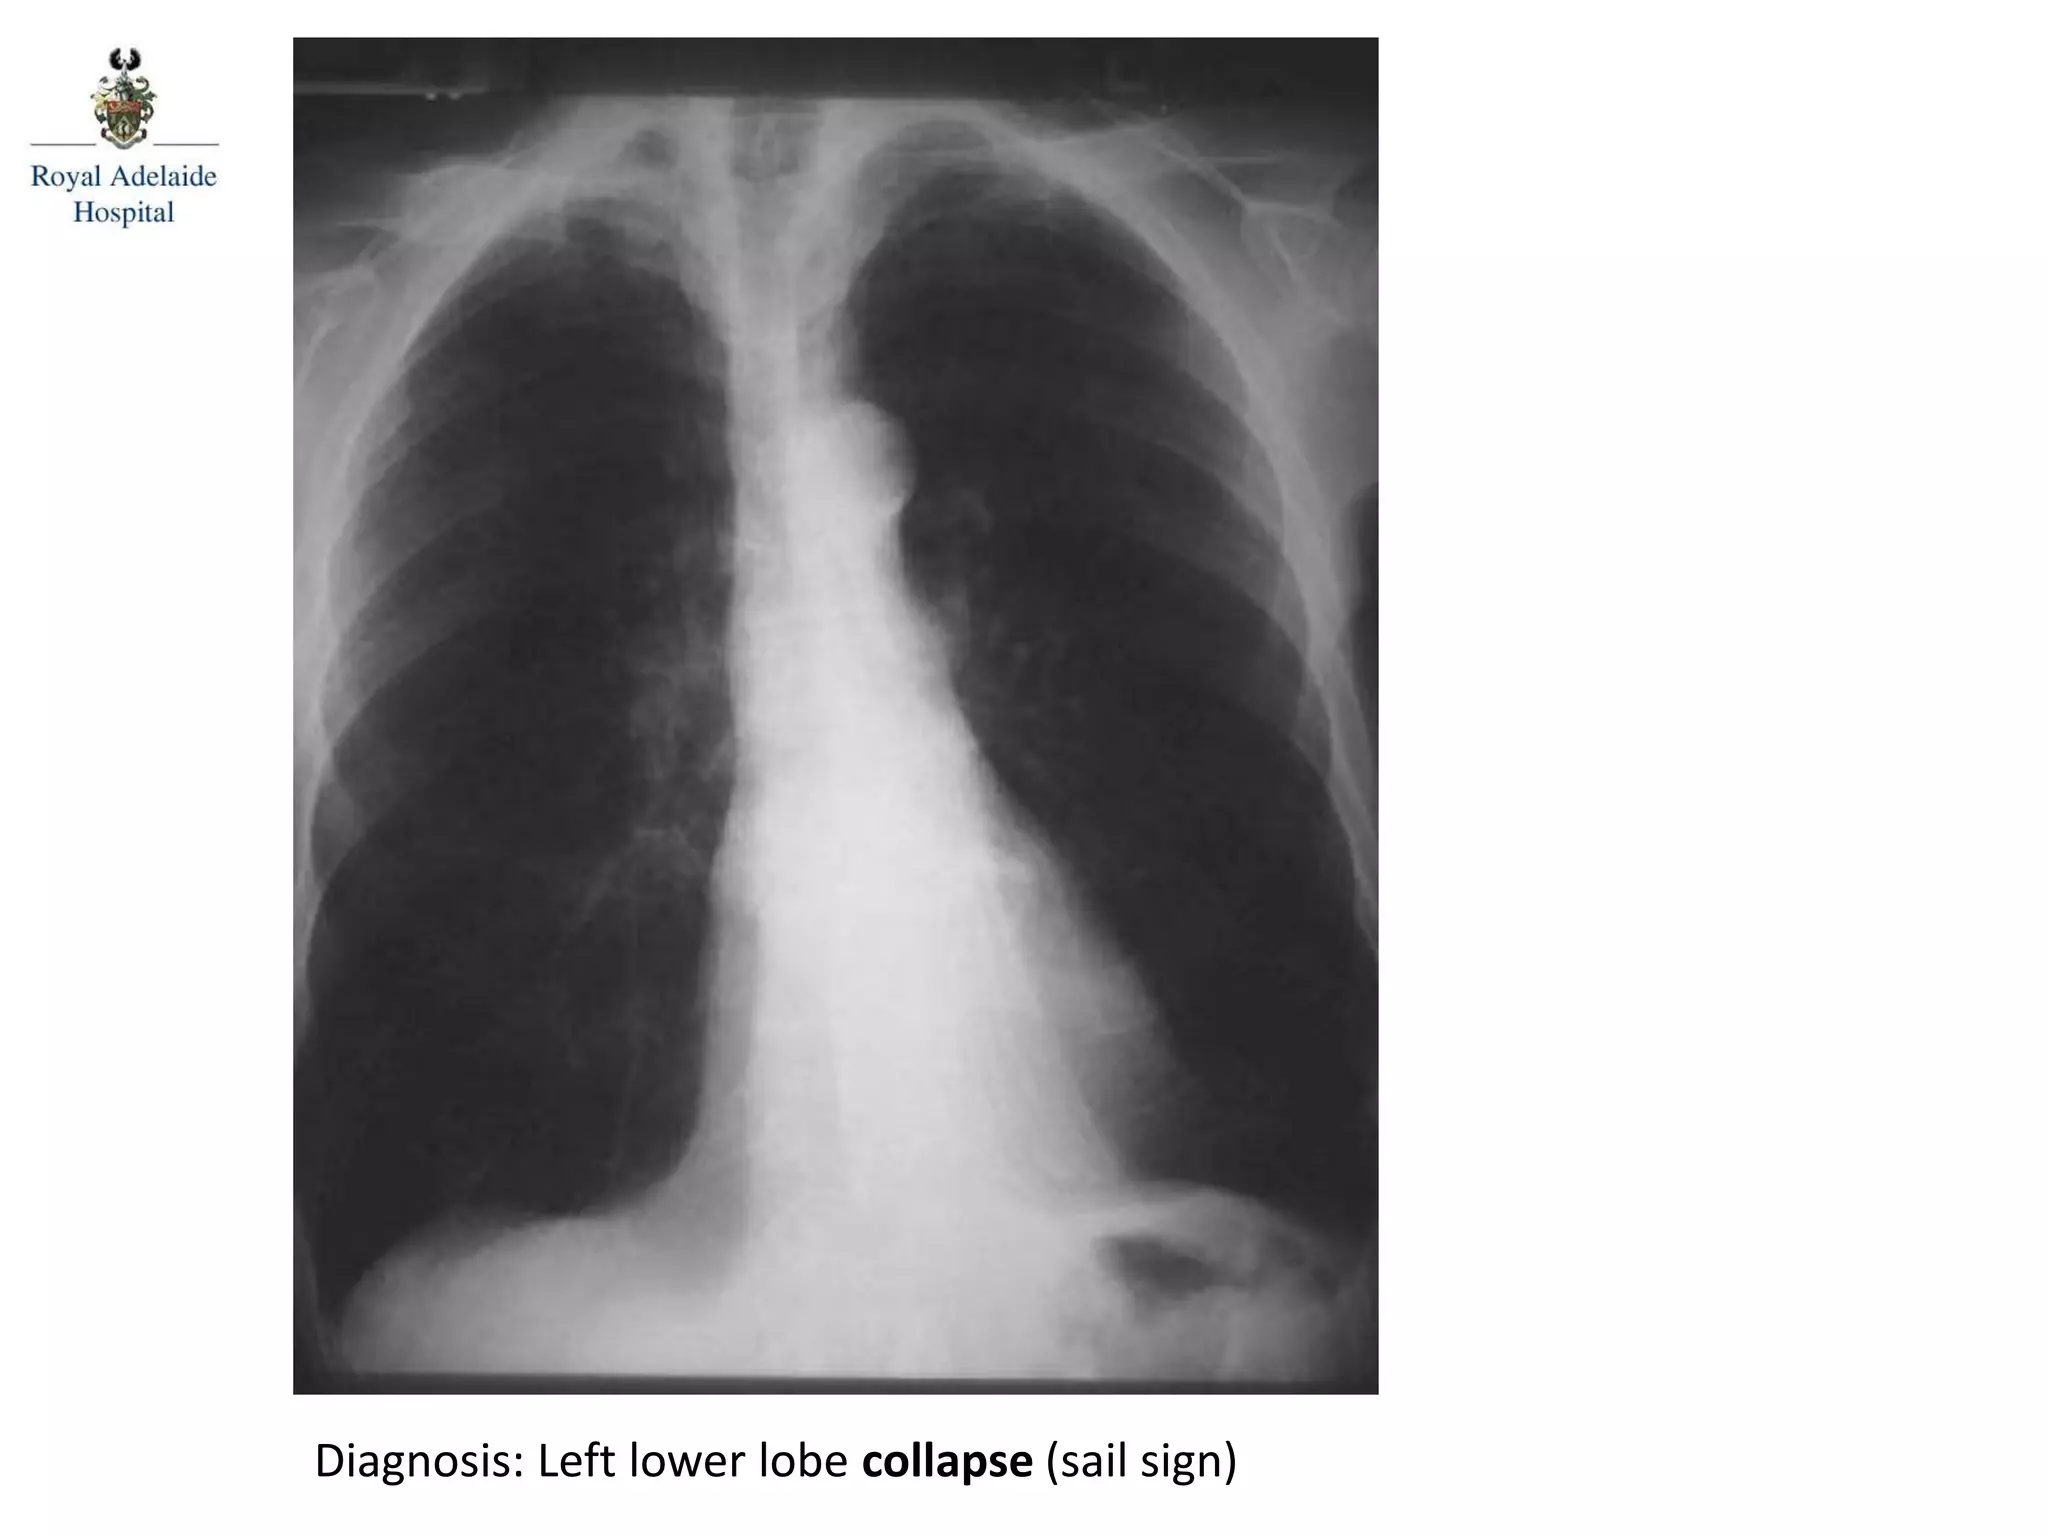

Diagnosis: Left lower lobe collapse (sail sign)